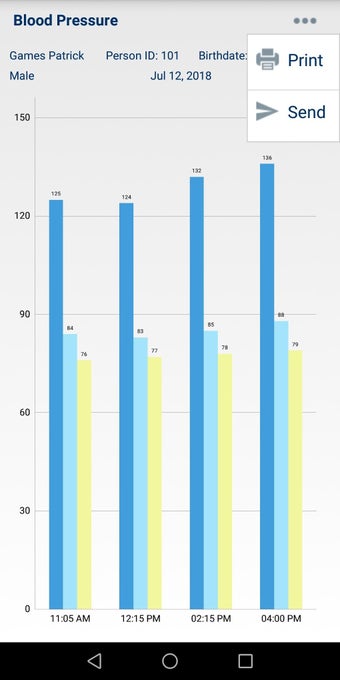

In addition, the app has a blood pressure module that measures systolic, diastolic, and pulse, and allows users to export blood pressure reports to either PDF or graphs. The app also has a blood glucose (sugar) module that records blood sugar values and allows users to export blood glucose reports to either PDF or graphs. Users can also send blood pressure and blood sugar reports to their doctor. The app is compatible with multiple screens, including phones and tablets, and works on Chromebook systems. Overall, the Android Medical Records App is a great tool for patients and physicians alike for managing patient information and medical records.